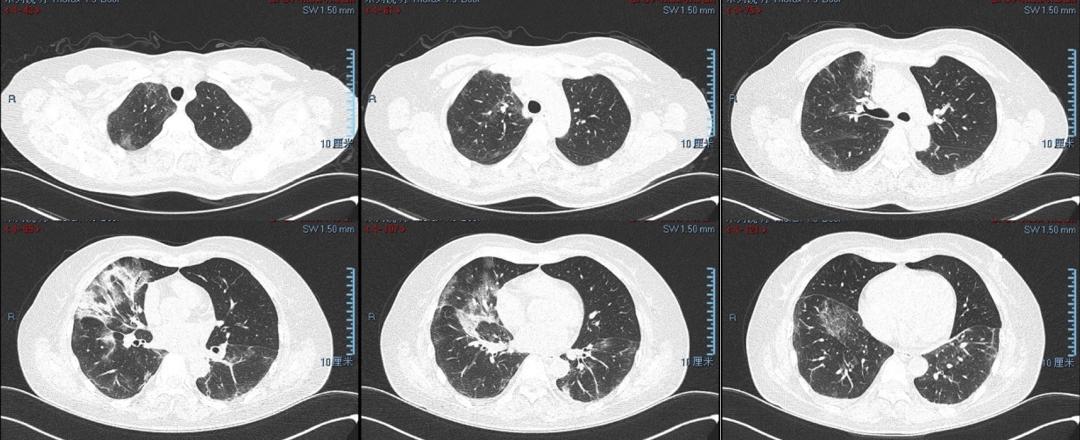

图1 胸部CT平扫(2023年1月30日)

现病史: 患者2月余前(2022年12月25日)出现间断发热,体温最高38.5℃,伴干咳、乏力及周身酸痛,自服退热药物后体温可降至正常,1周后上述症状改善,未就医。2周后(2023年1月8日)再次出现发热,体温最高39℃,伴干咳,口咽拭子新冠核酸阳性,当地诊所予口服阿兹夫定5mg/日 7天,效果不佳。2023年1月19日就诊当地医院,查血常规大致正常(WBC 7.52×10^9/L,Neu 76.7%,Lym 1.14×10^9/L,CRP 9.39mg/L),胸部CT提示双下肺磨玻璃影(未见原片),予静点甲强龙40mg/日 3天,然后减量为20mg/日 7天。但是治疗效果不佳,仍间断发热。1月前(2023年1月30日)转至上级医院,复查胸部CT提示双肺多发磨玻璃、渗出及实变影。